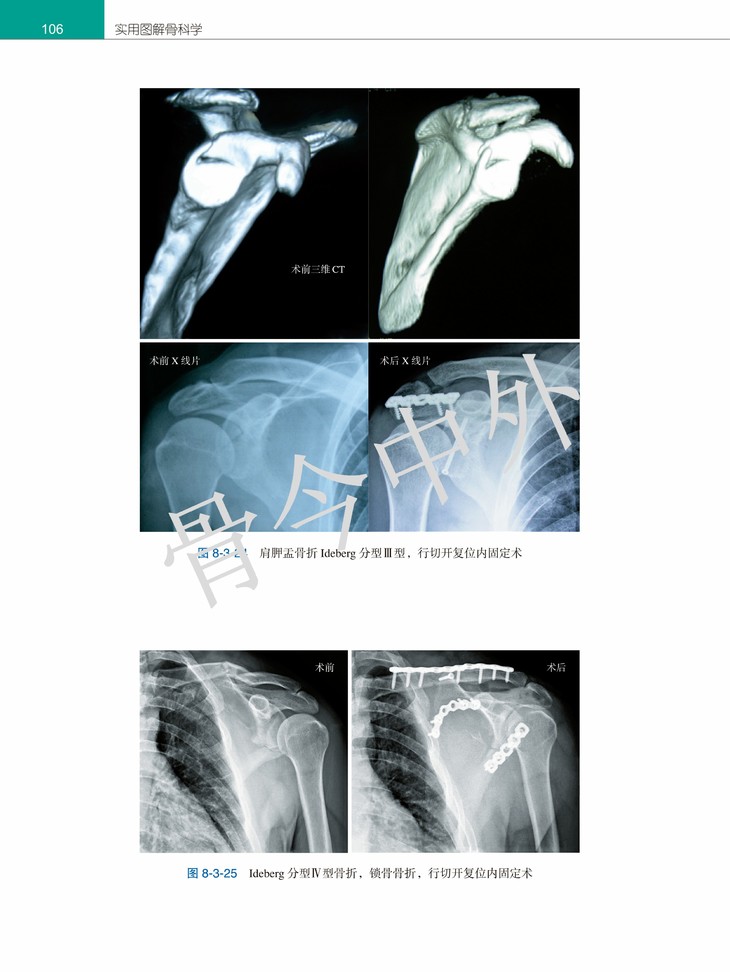

▷ 图文并茂,引经据典,全书2000余幅精美图片,便于阅读和理解。